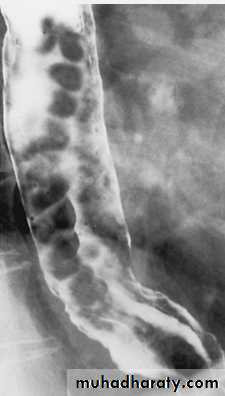

• Stricture: benign and malignant / causes / specific location

Stricture

Benign vs. malignant Causes Specific locationContrast study EUS CT